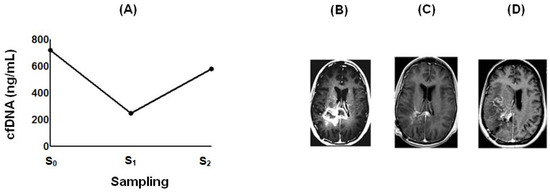

2.4. Effect of POH-Based Therapy on cfDNA Levels and the Disease Process